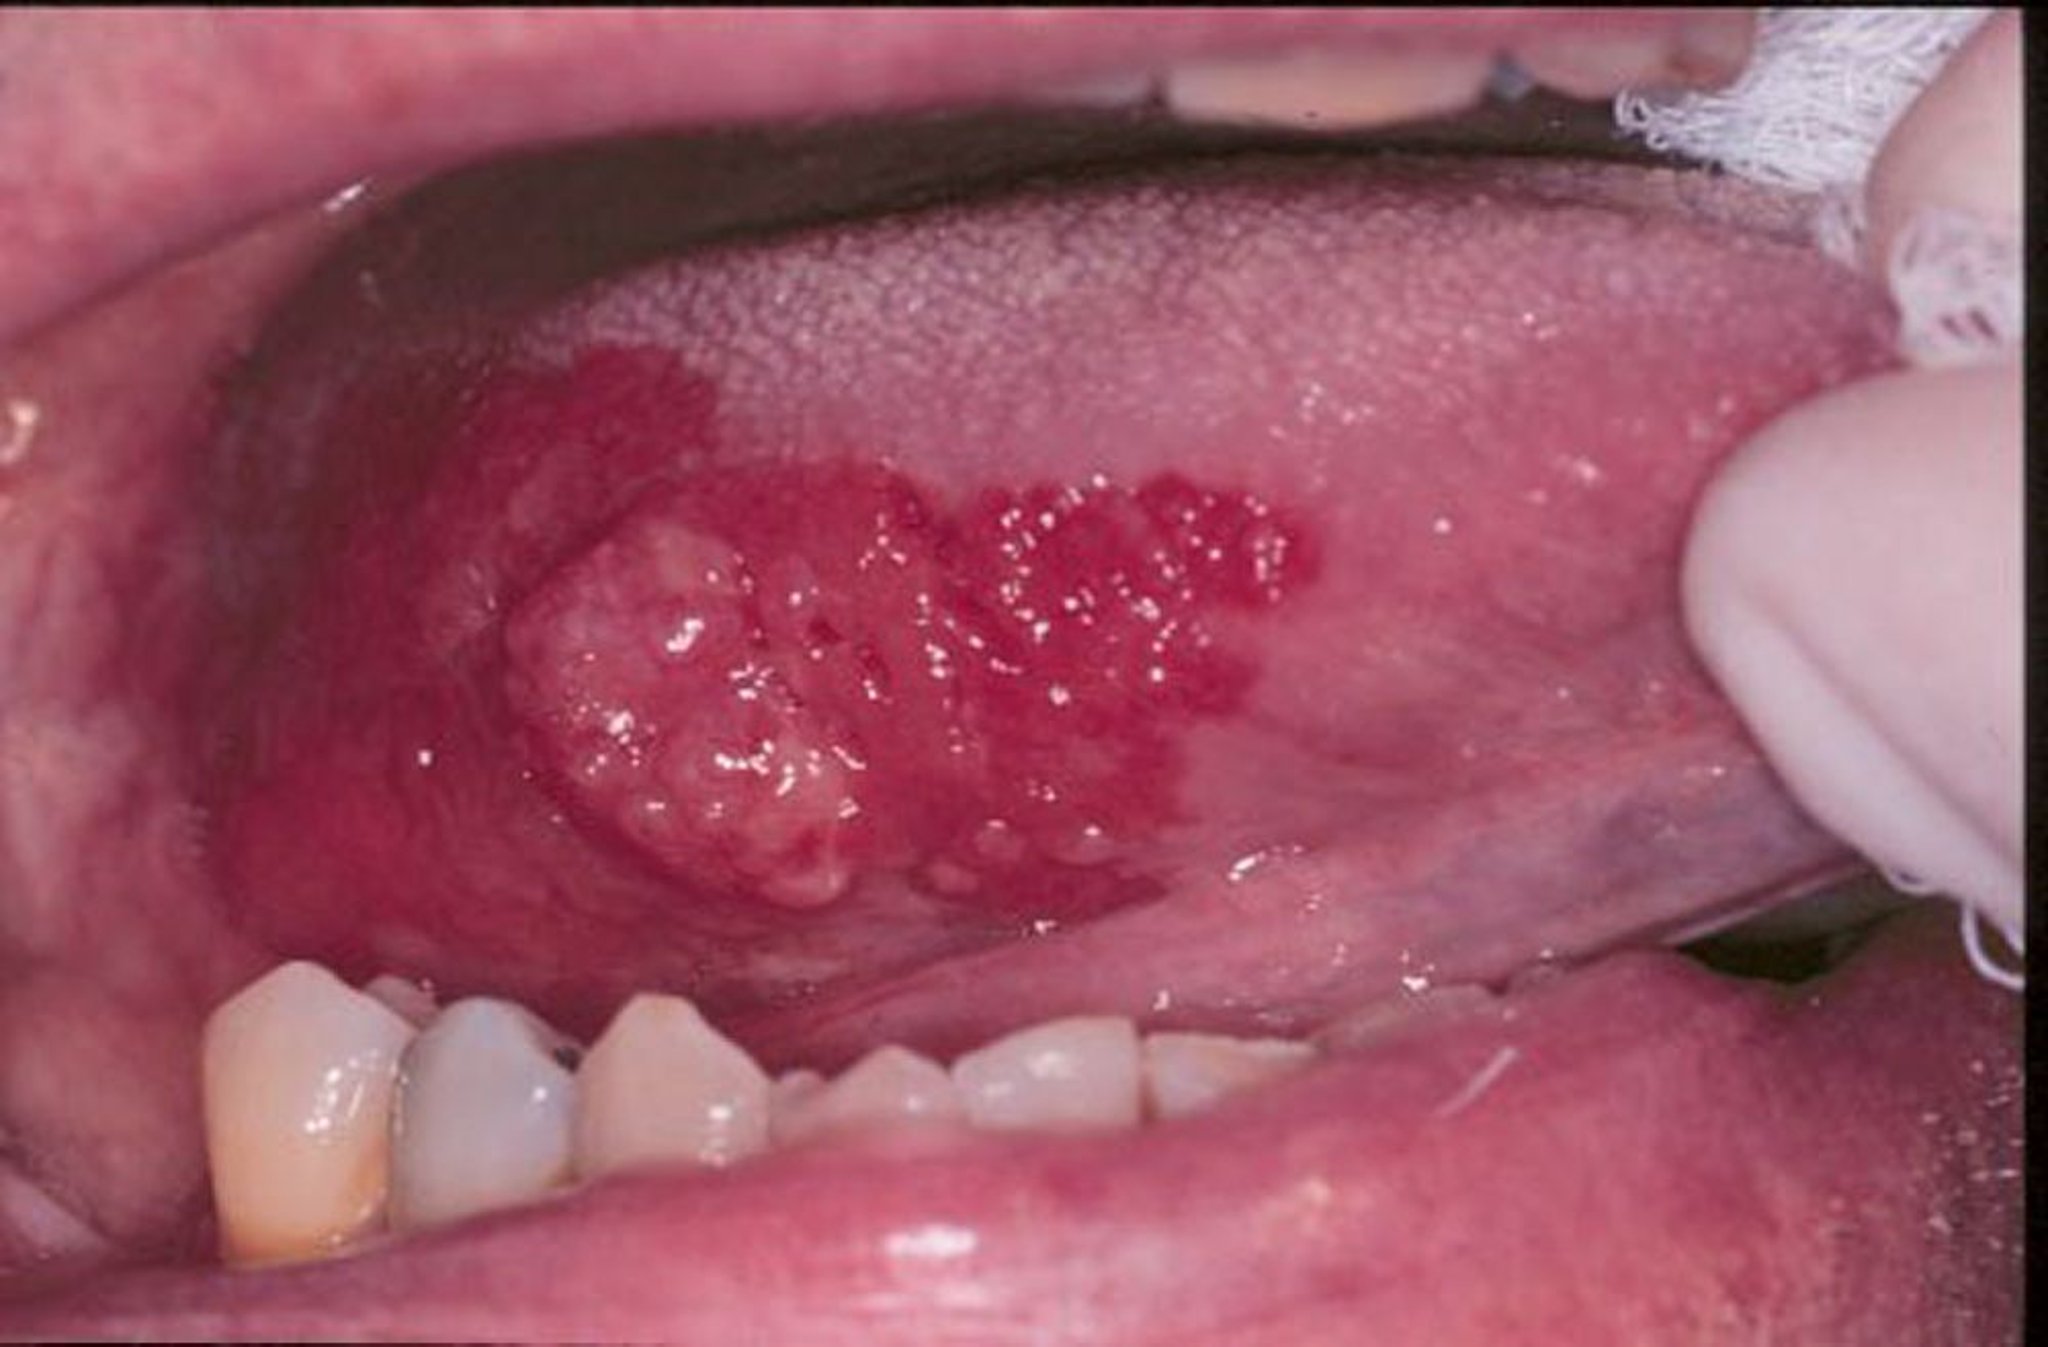

Эритроплакия и плоскоклеточная карцинома

Лейкоплакия является общим термином, которым можно описать белые гиперкератозные бляшки, развивающиеся в ротовой полости. На этом изображении экзофитный плоскоклеточный рак языка окружен областью эритроплакии.

Image provided by Jonathan A. Ship, DMD.